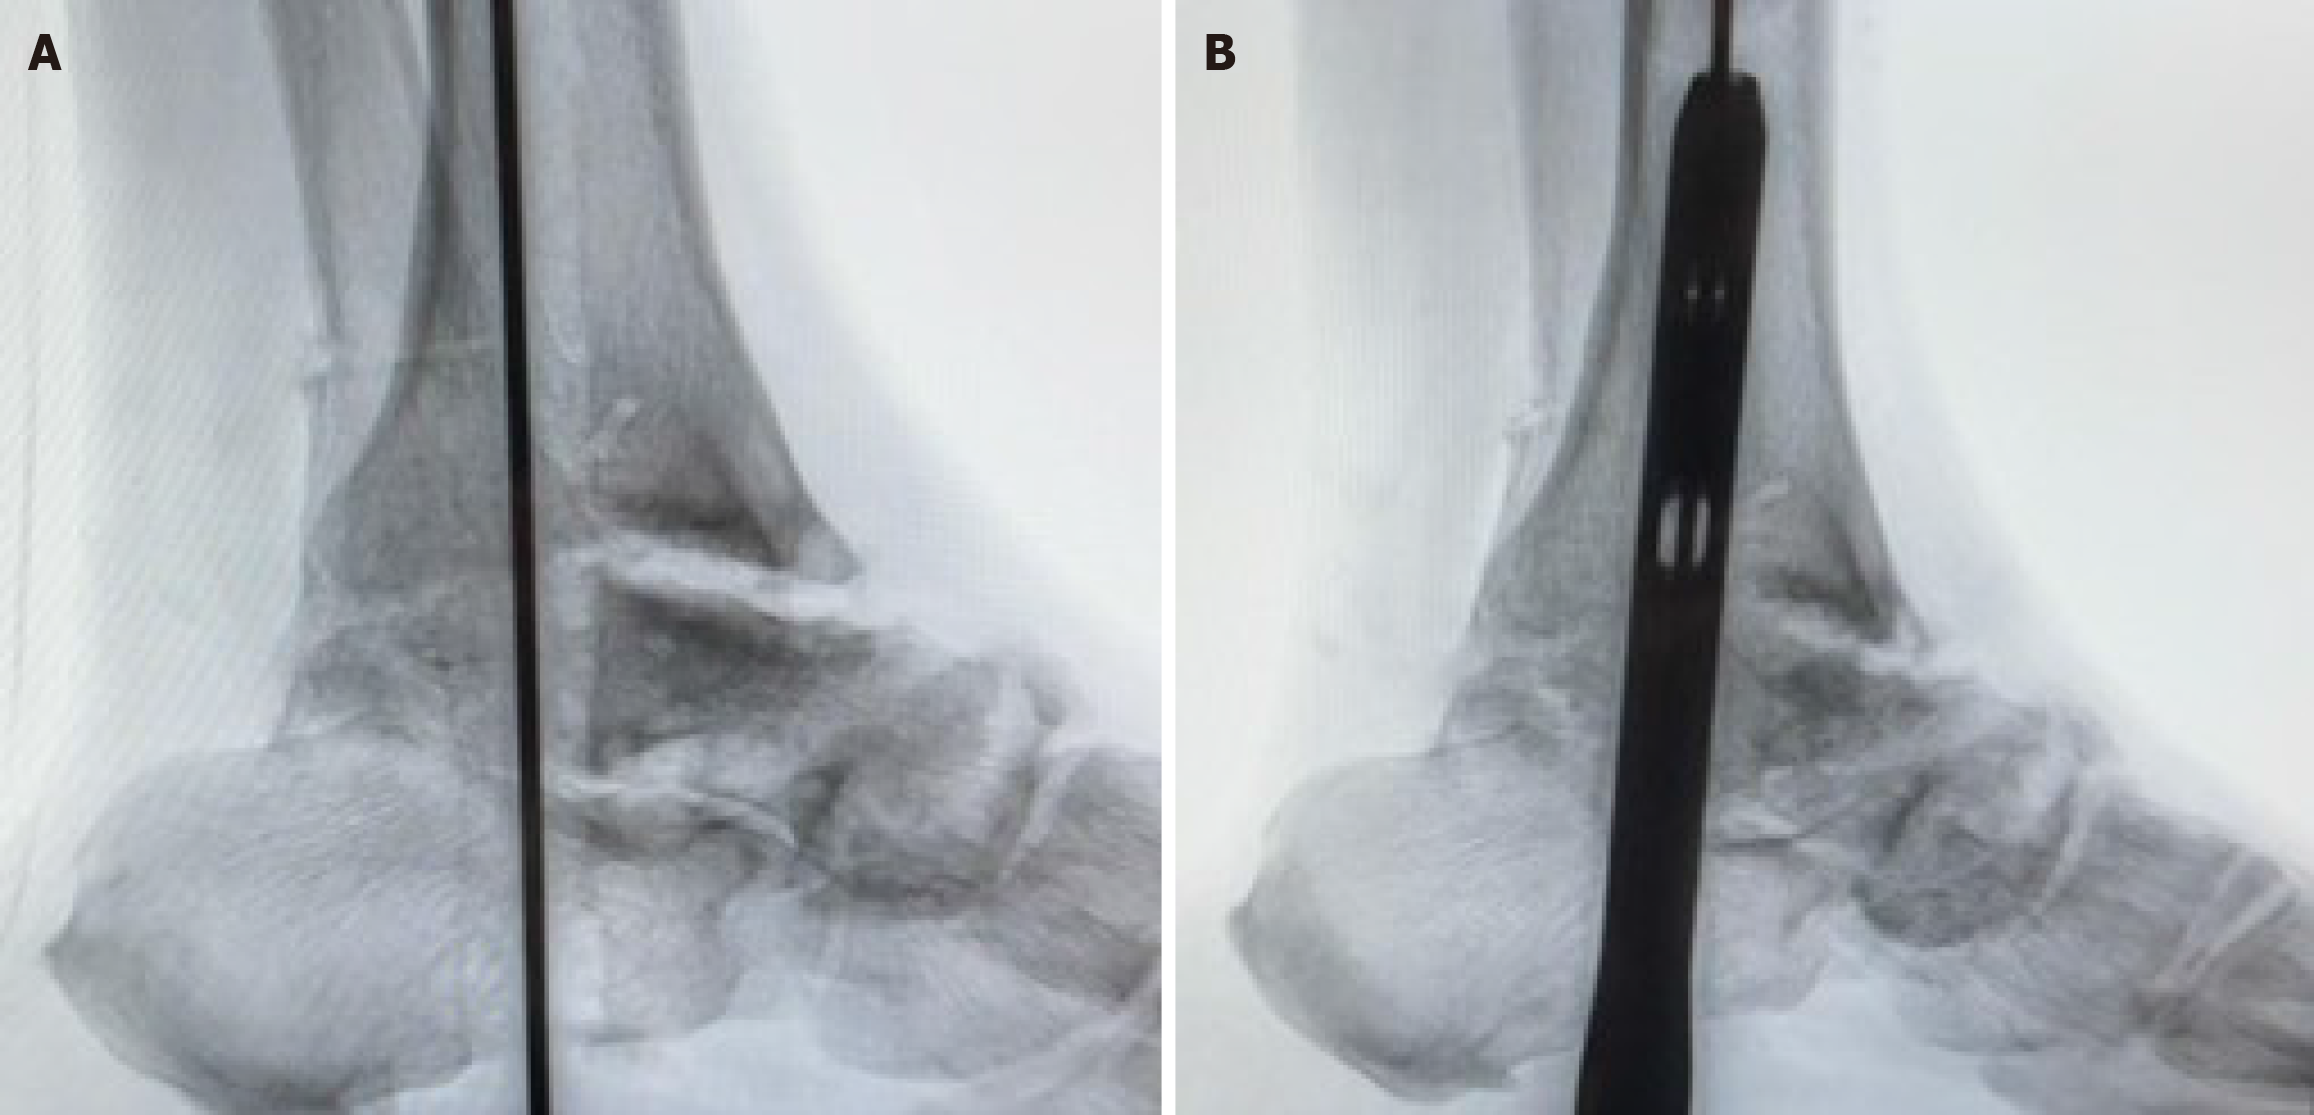

Step 1: Transmalleolar approach with periosteal preservation: The surgical approach was initiated through a lateral transmalleolar incision with a controlled lateral malleolar osteotomy performed approximately 2-4 cm proximal to the ankle joint line using an oscillating saw with the cut made perpendicular to the long axis of the fibula. The critical innovation involves opening the syndesmosis from anterior to facilitate preparation, followed by careful sliding and eversion of the fibula downward while maintaining its attachment to all related anatomical structures. Meticulous attention was paid to preserving the periosteal attachment and vascular supply to the entire distal osteotomized fragment, ensuring the fibular segment remained viable as a vascularized flap. This was achieved by careful subperiosteal dissection and protection of the perforating branches of the peroneal artery. This technique allows the preserved lateral malleolus to be retracted posteriorly using a Hohmann retractor, providing excellent visualization and access to both the ankle and subtalar joint complexes while maintaining the biological viability of the malleolar fragment for subsequent reconstruction and enhanced healing potential (Figures 1 and 2).

Step 3: Guide wire insertion and retrograde intramedullary nail placement: Under fluoroscopic guidance a guide wire was inserted through the plantar aspect of the calcaneus and advanced across the subtalar and ankle joints into the tibial medullary canal. Following sequential reaming, an appropriately sized retrograde intramedullary nail was inserted and advanced until adequate purchase was achieved in the tibial metaphysis with final positioning confirmed fluoroscopically (Figure 3).

At the final follow-up successful TTC fusion was achieved in all 24 patients (100%). Fusion was confirmed by robust bony bridging across ankle and subtalar joints on both plain radiographs and CT scans, demonstrating complete osseous consolidation in the entire cohort.